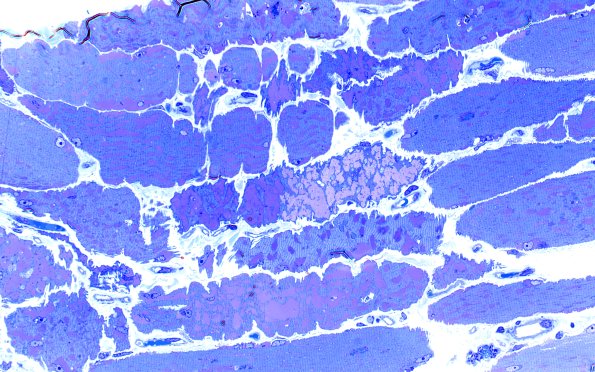

5C4 Muscle (Case 5) Plastic 40X 3

5C4,5 A variety of atrophic fibers with variable levels of stored material are shown. (Plastic sections)